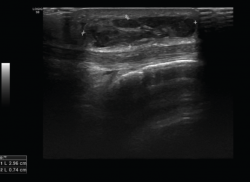

4. Prótesis (Figura 27)

Figura 27. Corte de reconstrucción sagital y coronal de tomografía axial computarizada de rodilla: se valoran los componentes femoral y tibial de la prótesis total.